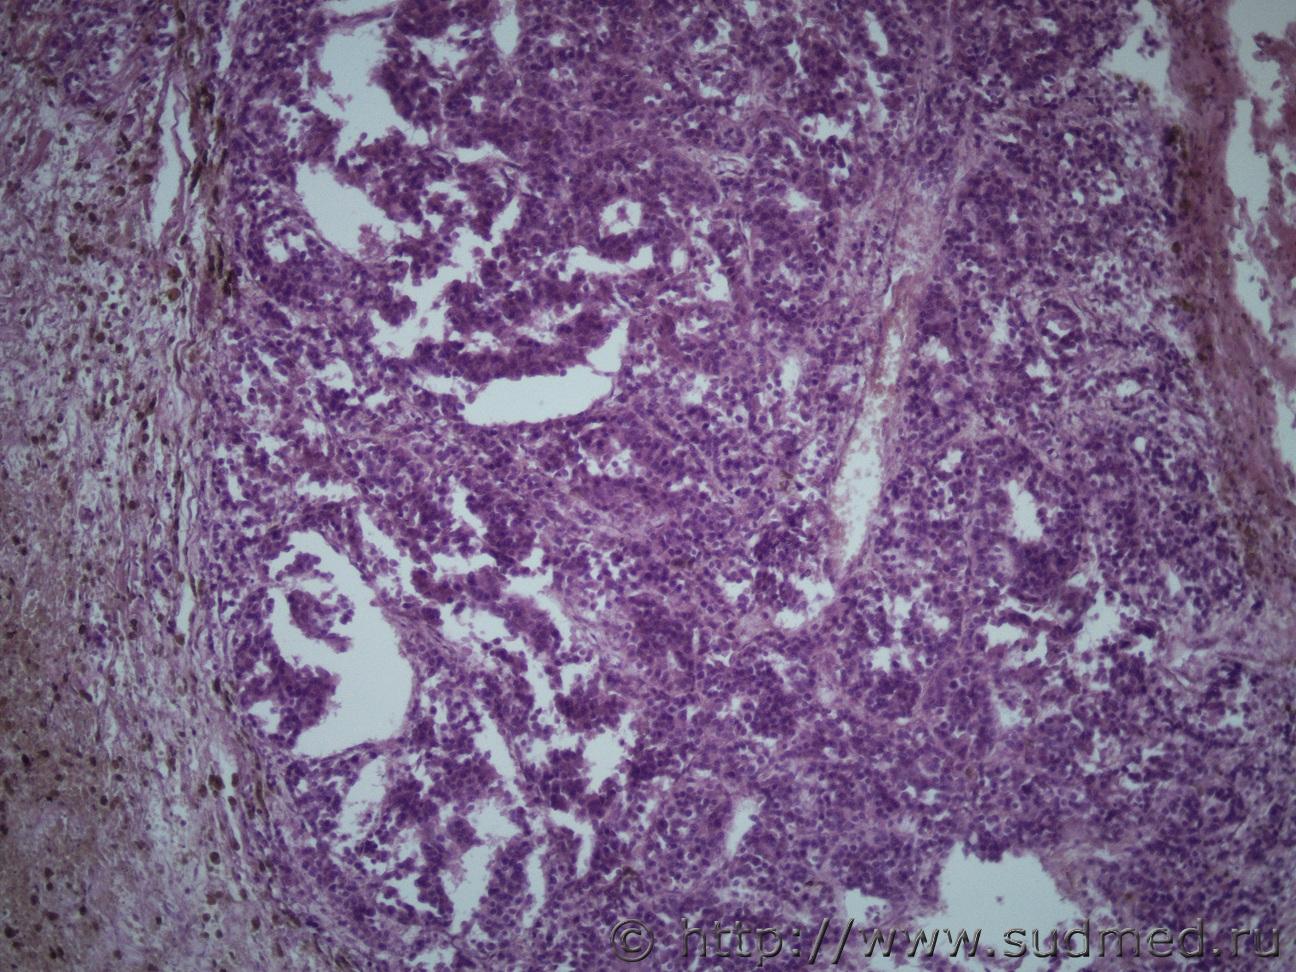

Рак предстательной железы

Ув. коллеги помогите определиться с раком. Муж 60 лет. Новообразование предстательной железы с метастазами в легкие, печень, диафрагмуСудебная медицина - Прикрепленное изображение Судебная медицина - Прикрепленное изображениеСудебная медицина - Прикрепленное изображениеСудебная медицина - Прикрепленное изображениеСудебная медицина - Прикрепленное изображение

Судебная медицина - Прикрепленное изображениеСудебная медицина - Прикрепленное изображениеСудебная медицина - Прикрепленное изображение ПеченьСудебная медицина - Прикрепленное изображение Судебная медицина - Прикрепленное изображение